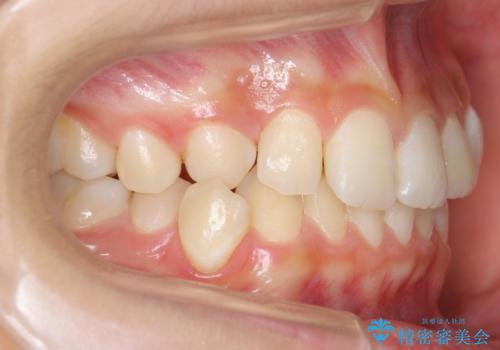

埋まっている犬歯を抜歯して、歯列矯正

- 右上の犬歯が埋伏していたため、抜歯しました。

その後、右下の小臼歯を1本抜歯し、ワイヤー矯正を行いました。

犬歯の代わりに小臼歯を配列し、最小限の抜歯の本数としました。

犬歯の両側の歯に関しては移動することにより歯槽骨が順調に回復し、上顎洞底の形態にかかわらず歯根のパラレリングを行うことができました。